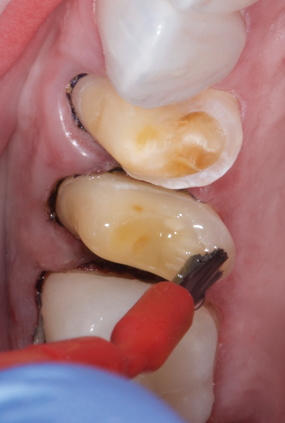

(5.) Step C: the restorations are inserted with a dual-cure composite resin, and the excess composite material is cleaned with a sable brush.

Figure 5